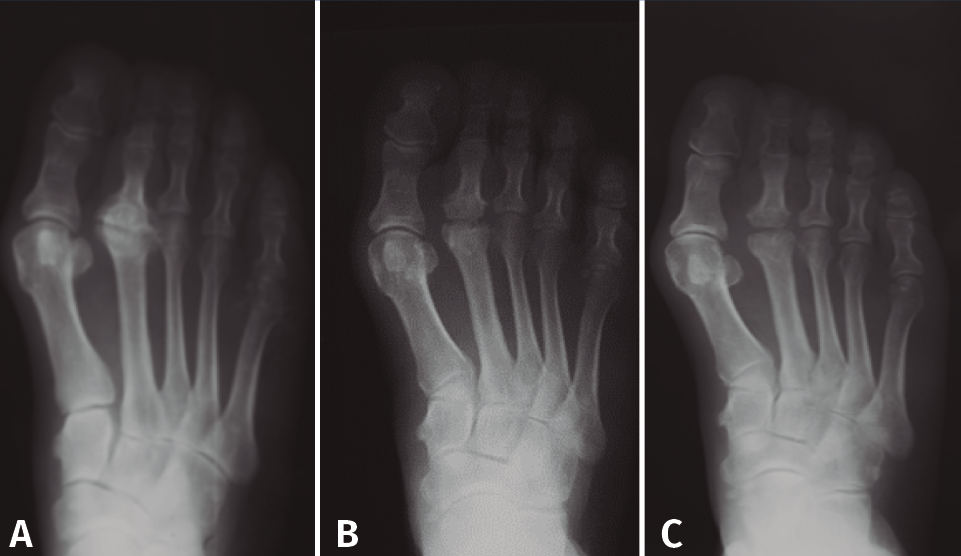

Figura 4. Estadios de Smillie. A: estadio I; B: estadio II; C: estadio III; D: estadio IV; E: estadio V.

Basándose en la historia natural de la enfermedad y atendiendo a los cambios radiológicos, Smillie(16) clasifica, con propósito terapéutico, la lesión en 5 estadios (Figura 4):

- Estadio 1: aparece una línea de fractura a través de la epífisis.

- Estadio 2: se produce una depresión central de la cabeza por colapso del hueso subcondral. El espacio articular puede ensancharse.

- Estadio 3: la depresión central hace que se proyecten hacia delante los bordes medial y lateral de la cabeza, manteniéndose intacta la parte plantar.

- Estadio 4: la parte central necrosada de la cabeza puede desprenderse de la parte plantar, formándose un cuerpo libre articular.

- Estadio 5: aplanamiento de la cabeza metatarsal y van apareciendo los cambios degenerativos secundarios.